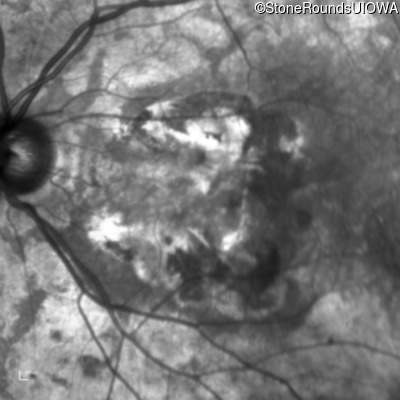

Age at visit: 64 years

This 64 year old woman first noticed some distortion in her vision at age 46 while looking at graph paper.

Age at visit: 65 years

Age at visit: 66 years

Age at visit: 70 years